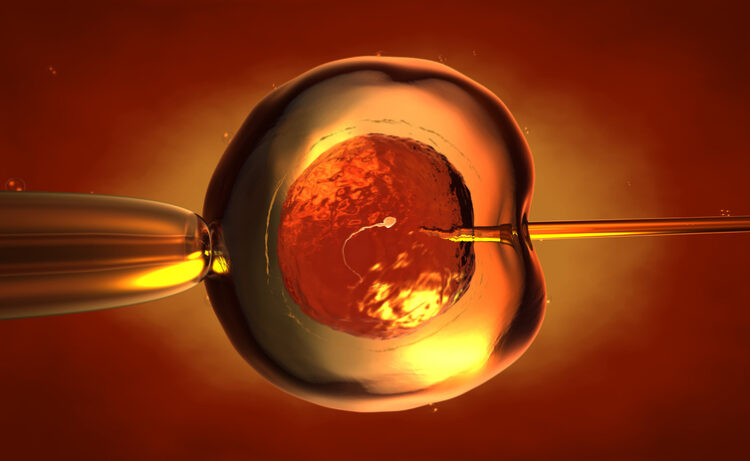

연구진은 감수분열이라는 과정과 관련된 난자의 취약점을 표적으로 삼았다. 감수분열은 생식세포(난자 또는 정자)가 유전 물질의 절반을 버리고 결합해 배아를 형성하는 과정이다.

난자의 경우, 이를 위해서는 23쌍의 X자형 염색체가 세포 내 단일 축을 따라 정렬돼야 한다. 수정이 일어나면 세포가 분열하면서 염색체 쌍이 이상적으로는 중심을 따라 결합돼 난자로부터 23개의 단일 염색체를, 나머지는 정자로부터 전달받은 염색체를 가진 세포가 만들어진다.

그러나 오래된 난자에서는 염색체 쌍이 중간 지점에서 느슨해져서 수정 전에 약간 분리되거나 완전히 떨어져 나가는 경향이 있다. 이렇게 되면 X자 모양의 구조가 제대로 정렬되지 않고 세포 내에서 무질서하게 움직이게 돼 세포 분열 시 대칭적으로 분열되지 않는다. 결과적으로 염색체 수가 너무 많거나 너무 적은 배아가 생성된다.

연구진은 염색체 쌍을 접착하는 역할을 하는 것으로 보이는 단백질인 슈고신 1이 나이가 들면서 감소한다는 사실을 발견했다. 생쥐와 인간의 난자를 이용한 실험에서 슈고신 1을 미세 주입하면 염색체 쌍이 조기에 분리되는 문제를 되돌릴 수 있는 것으로 나타났다. 연구진은 불임 클리닉 환자들이 기증한 난자를 대상으로 단백질 주입 치료를 했다.

연구 결과 배아의 유전적 오류를 유발하는 노화 관련 결함이 난자에 필수 단백질을 보충함으로써 되돌릴 수 있는 것으로 나타났다. 난임 환자들이 기증한 난자에 해당 단백질을 미세 주입한 결과, 처리하지 않은 난자에 비해 결함 발생률이 거의 절반으로 감소했다. 구체적으로 치료를 받았을 때 결함이 있는 난자의 비율이 53%에서 29%로 감소했다.